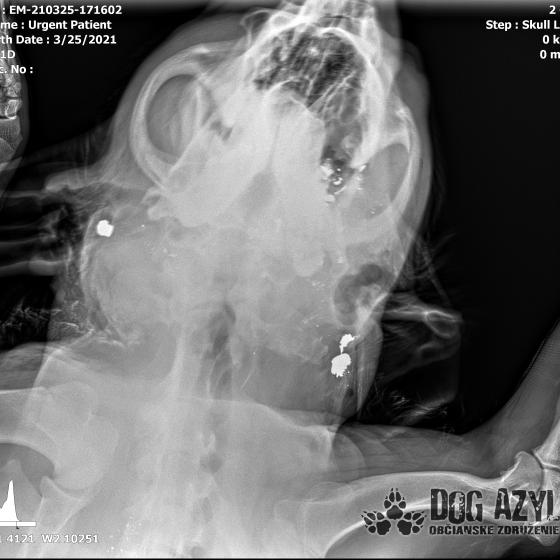

/Strašne to chcem dopísať tak, aby to bolo čitateľné a pochopiteľné, ale celá sa klepem od zlosti a nevidím cez slzy.../ Lebo Ona už meno nikdy nebude mať.. On dostal meno Baris a bojuje o život!!! Má dolámanú sánku a je v šoku!!! Dostal prvú pomoc, analgetiká a priorita bola znížiť jeho teplotu z 41,4°C!!!

Ústami nevie pohnúť, jazyk si nevie ovládať a tak sa sám nedokáže schladiť ani napiť. Podľa RTG sú srdiečko a pľúca v poriadku, ale vôbec nemá vyhraté!!! Niekto chcel Barisa zlikvidovať, ale my za neho budeme bojovať do posledného dychu!!! Zajtra bude prevezený na veterinárnu kliniku Sibra centrum, kde ho čaká team špecialistov z oblasti chirurgie, neurológie a ortopédie. Ak je čo i len najmenšia nádej, že Baris bude môcť žiť, tak BARIS BUDE ŽIŤ!!!